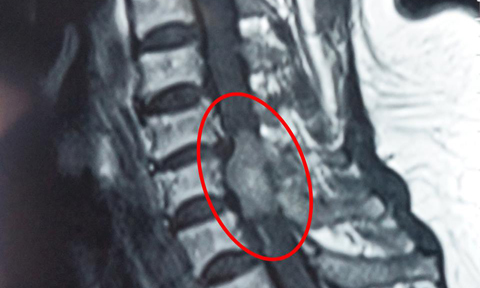

Kết quả kiểm tra cho thấy, bệnh nhân có khối u rất lớn chèn ép vào tủy sống, phá hủy xương các đốt sống từ tháng 9 đến tháng 12.

Ekip quyết định mổ từ lưng, giải phóng chèn ép, bóc tách lấy sạch khối u kèm theo lấy một phần thân các đốt sống từ T9 đến T12 bị mủn nát. Phần còn lại của đốt sống còn khá nhiều nên không cần phải thay thân đốt sống. Ca mổ kéo dài hơn 5 giờ, khối u lấy ra có kích thước lên tới 12x5cm.